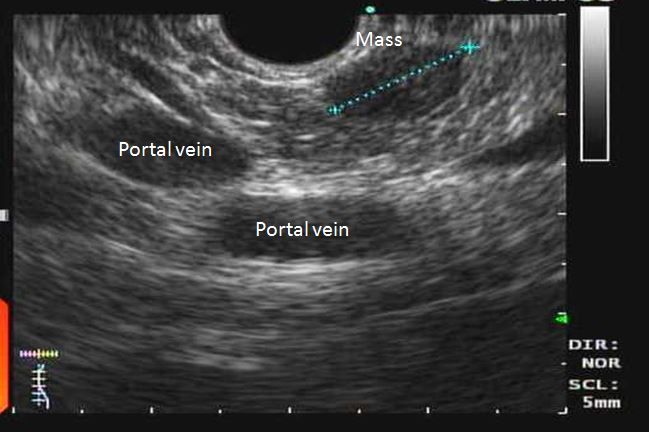

A 26-year-old woman experiences occasional blurring of her vision and palpitations. Her symptoms often improve after drinking juice. She does not have a history of diabetes mellitus. One day, she presents to the ER after experiencing a seizure. A head CT performed in the ER is negative. Her blood glucose level is 30 mg/dL, and she is given intravenous dextrose solution. During her workup, abdominal CT is performed and is notable for a mass in the head of the pancreas (Figure, broken blue line).

The most likely cause of this patient’s clinical presentation is an insulinoma, a rare islet tumor of the pancreas that is characterized by symptomatic hypoglycemia and inappropriately increased plasma insulin during an episode of spontaneous hypoglycemia. Insulinomas are evenly distributed in the pancreas; that is one-third are found in the head, one-third in the body, and one-third in the tail. On imaging, characteristic features of islet cell tumors, which include insulinomas, have a well-circumscribed and encapsulated appearance.